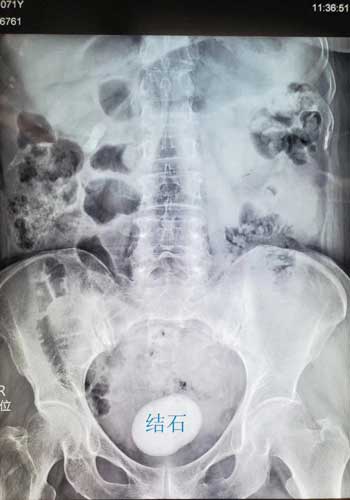

术前患者腹部平片所示膀胱内巨大结石。院方供图

“在详细询问患者的病史后,我们认为患者膀胱内巨大结石的形成可能与她既往发生脑梗导致神经源性下尿路功能障碍及长期的膀胱慢性感染有关。而且我们检查发现这颗巨大的结石已经占据了患者膀胱的大部分容积,所以导致患者出现了尿频、尿急、漏尿等症状,严重影响了患者的生存质量。同时,这个巨大结石对膀胱壁有着直接压迫作用,可能造成膀胱壁缺血坏死,甚至自发性破裂,后果不堪设想,必须马上进行手术。”泌尿外科主任靳文生解释道。